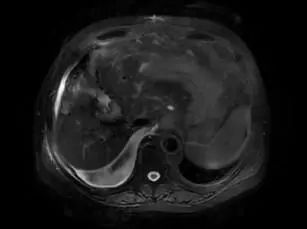

影像学评估:

图1. PET-MRI 功能影像特征